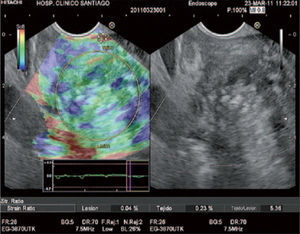

Elastografía cuantitativa guiada por ecoendoscopia (Q-EUS-E). Nuestro grupo20 presentó su experiencia acumulada mediante este método, que permite cuantificar la elasticidad tisular en el diagnóstico diferencial de lesiones sólidas pancreáticas. A través de un protocolo bien establecido de cálculo de un coeficiente de elasticidad o strain ratio (SR) y a partir de un punto de corte de 9,5 de un total de 199 pacientes con lesiones sólidas pancreáticas se obtiene, respectivamente, una sensibilidad, especificidad, VPP, VPN y eficacia global del 100, 91, 97, 100 y 98% en la detección de malignidad, confirmando resultados previamente publicados21 (fig. 1).